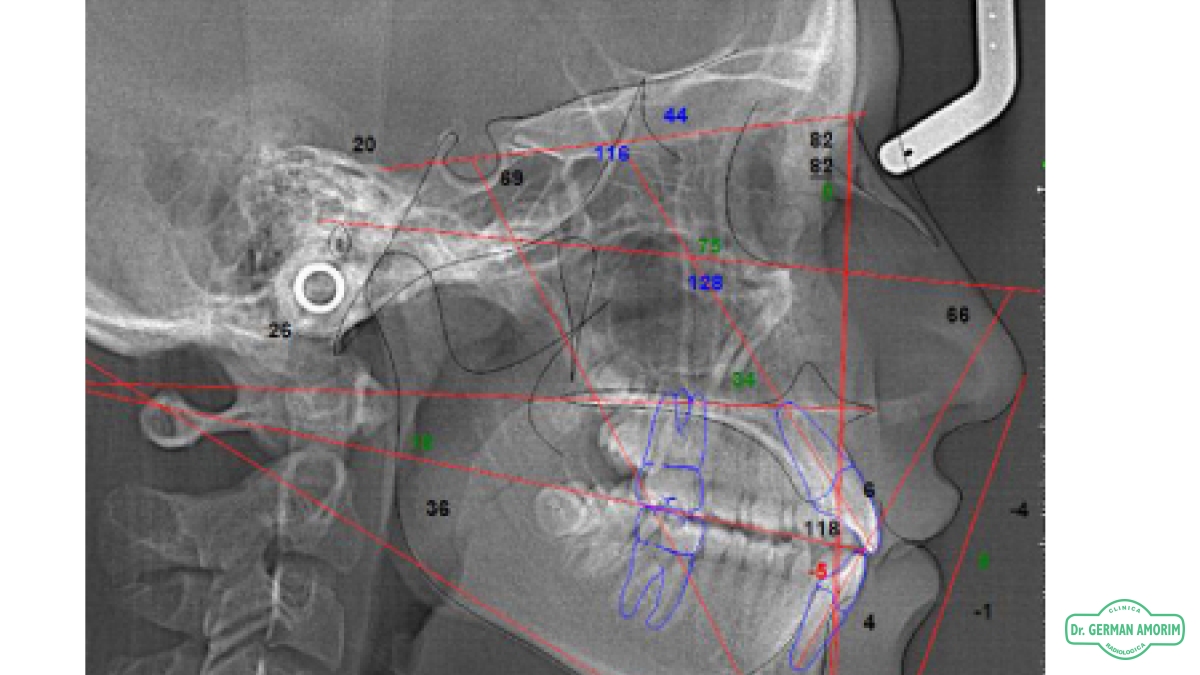

Estos estudios son una herramienta fundamental en el estudio de maloclusiones dentales y discrepancias esqueléticas, cuyo análisis se realiza mediante la identificación de puntos de referencia anatómicos en la radiografía del cráneo.

La calidad de la imagen que ofrece nuestro tomógrafo permite una ubicación más exacta de los puntos anatómicos lo cual es imprescindible para realizar el correcto diagnóstico en base a los estudios cefalométricos

Si la calidad de la imagen radiográfica no es adecuada, hay posibilidad de cometer errores lo que incide en la posibilidad de brindar un diagnóstico adecuado.

• Estudios cefalométricos